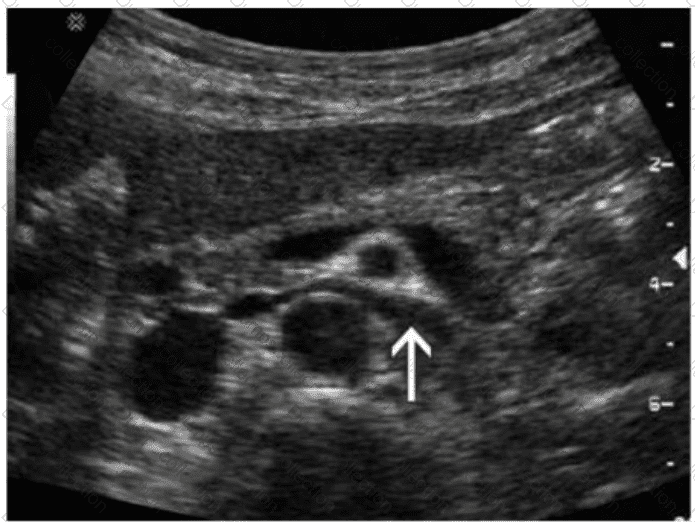

Which organ is drained via the vessel indicated by the arrow in this image?